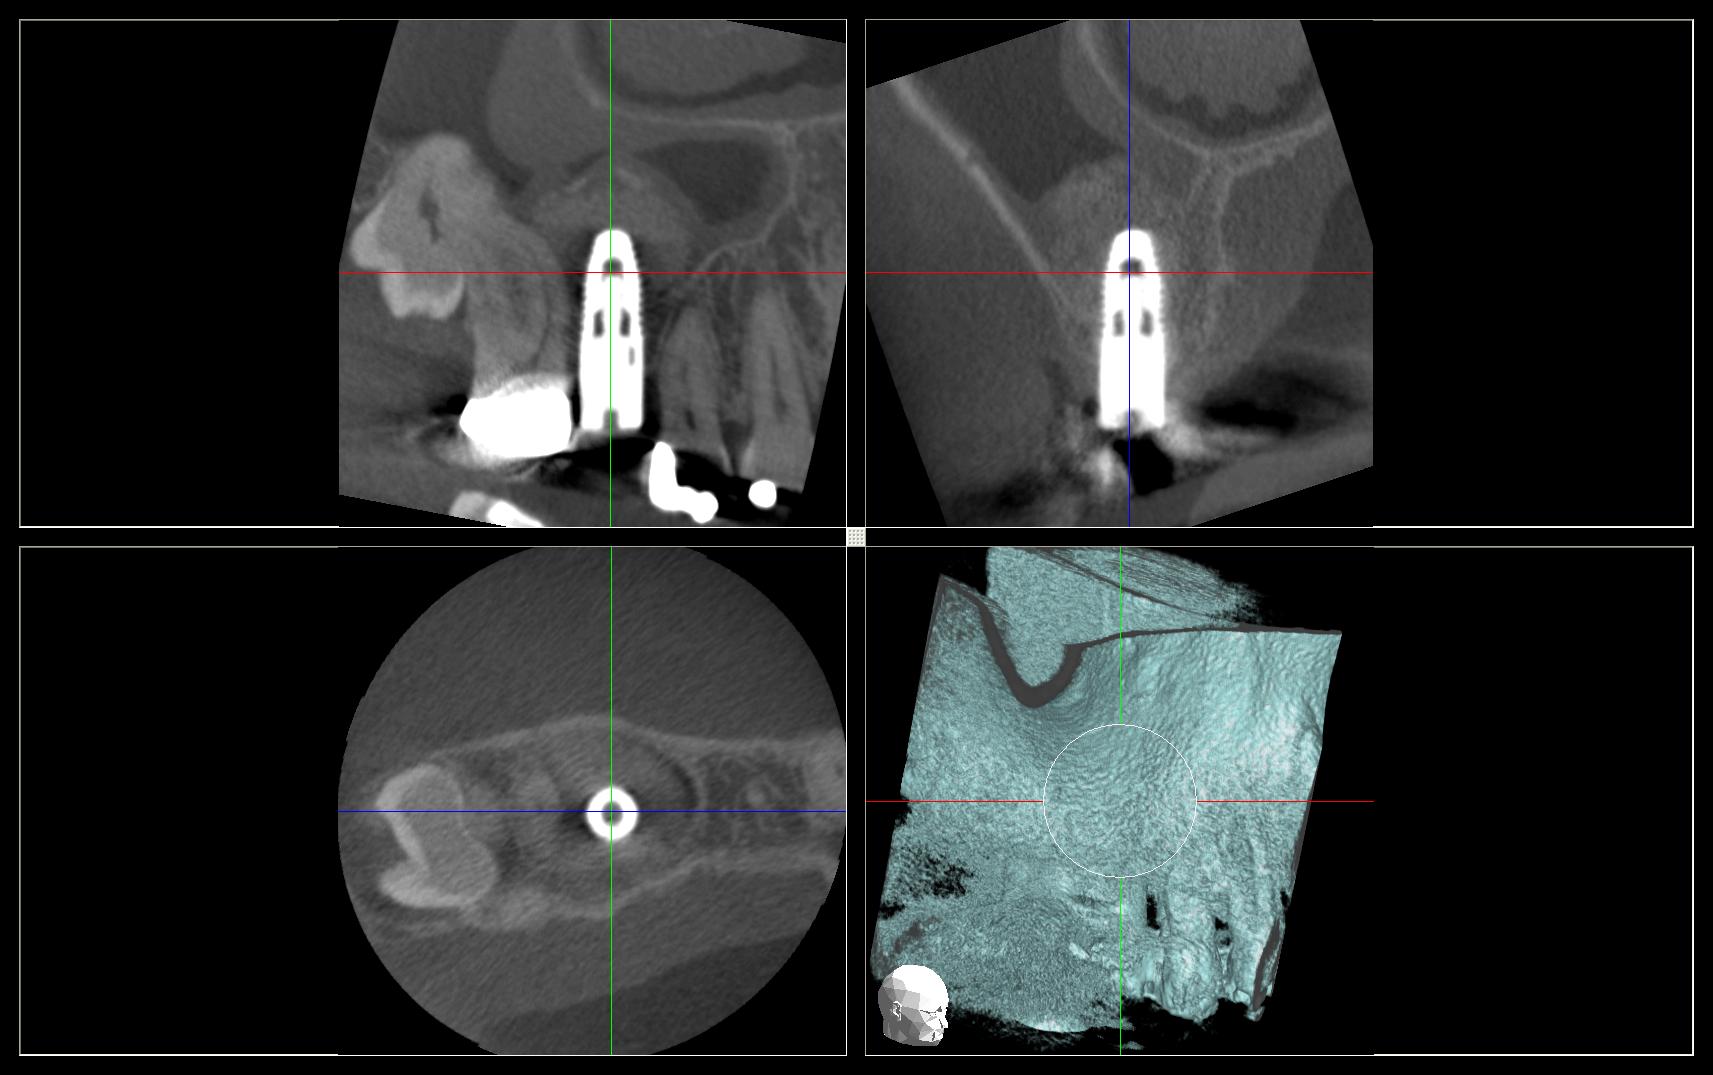

CBCT for Dentistry Dental Scanning Cavendish Imaging Dental Implant Artifact The aims of this study were to develop a computed tomography/magnetic resonance (ct/mr) oral. Titanium implants cause the greatest relative errors in se techniques. Cbct artifacts were investigated in images integrated at 0.25 mm, 10 mm, and 20 mm at regions of interest on concentric circles at. Metal artifact are common and decrease diagnostic value of ct images. Effectiveness of. Dental Implant Artifact.

Beam hardening artifacts by dental implants Comparison of conebeam Dental Implant Artifact Metal artifact are common and decrease diagnostic value of ct images. The aims of this study were to develop a computed tomography/magnetic resonance (ct/mr) oral. Effectiveness of dect and mar algorithms. Cbct artifacts were investigated in images integrated at 0.25 mm, 10 mm, and 20 mm at regions of interest on concentric circles at. Titanium implants cause the greatest relative. Dental Implant Artifact.

Sensors Free FullText Metal Artifact Reduction in Dental CBCT Dental Implant Artifact Cbct artifacts were investigated in images integrated at 0.25 mm, 10 mm, and 20 mm at regions of interest on concentric circles at. Metal artifact are common and decrease diagnostic value of ct images. Titanium implants cause the greatest relative errors in se techniques. The aims of this study were to develop a computed tomography/magnetic resonance (ct/mr) oral. Effectiveness of. Dental Implant Artifact.